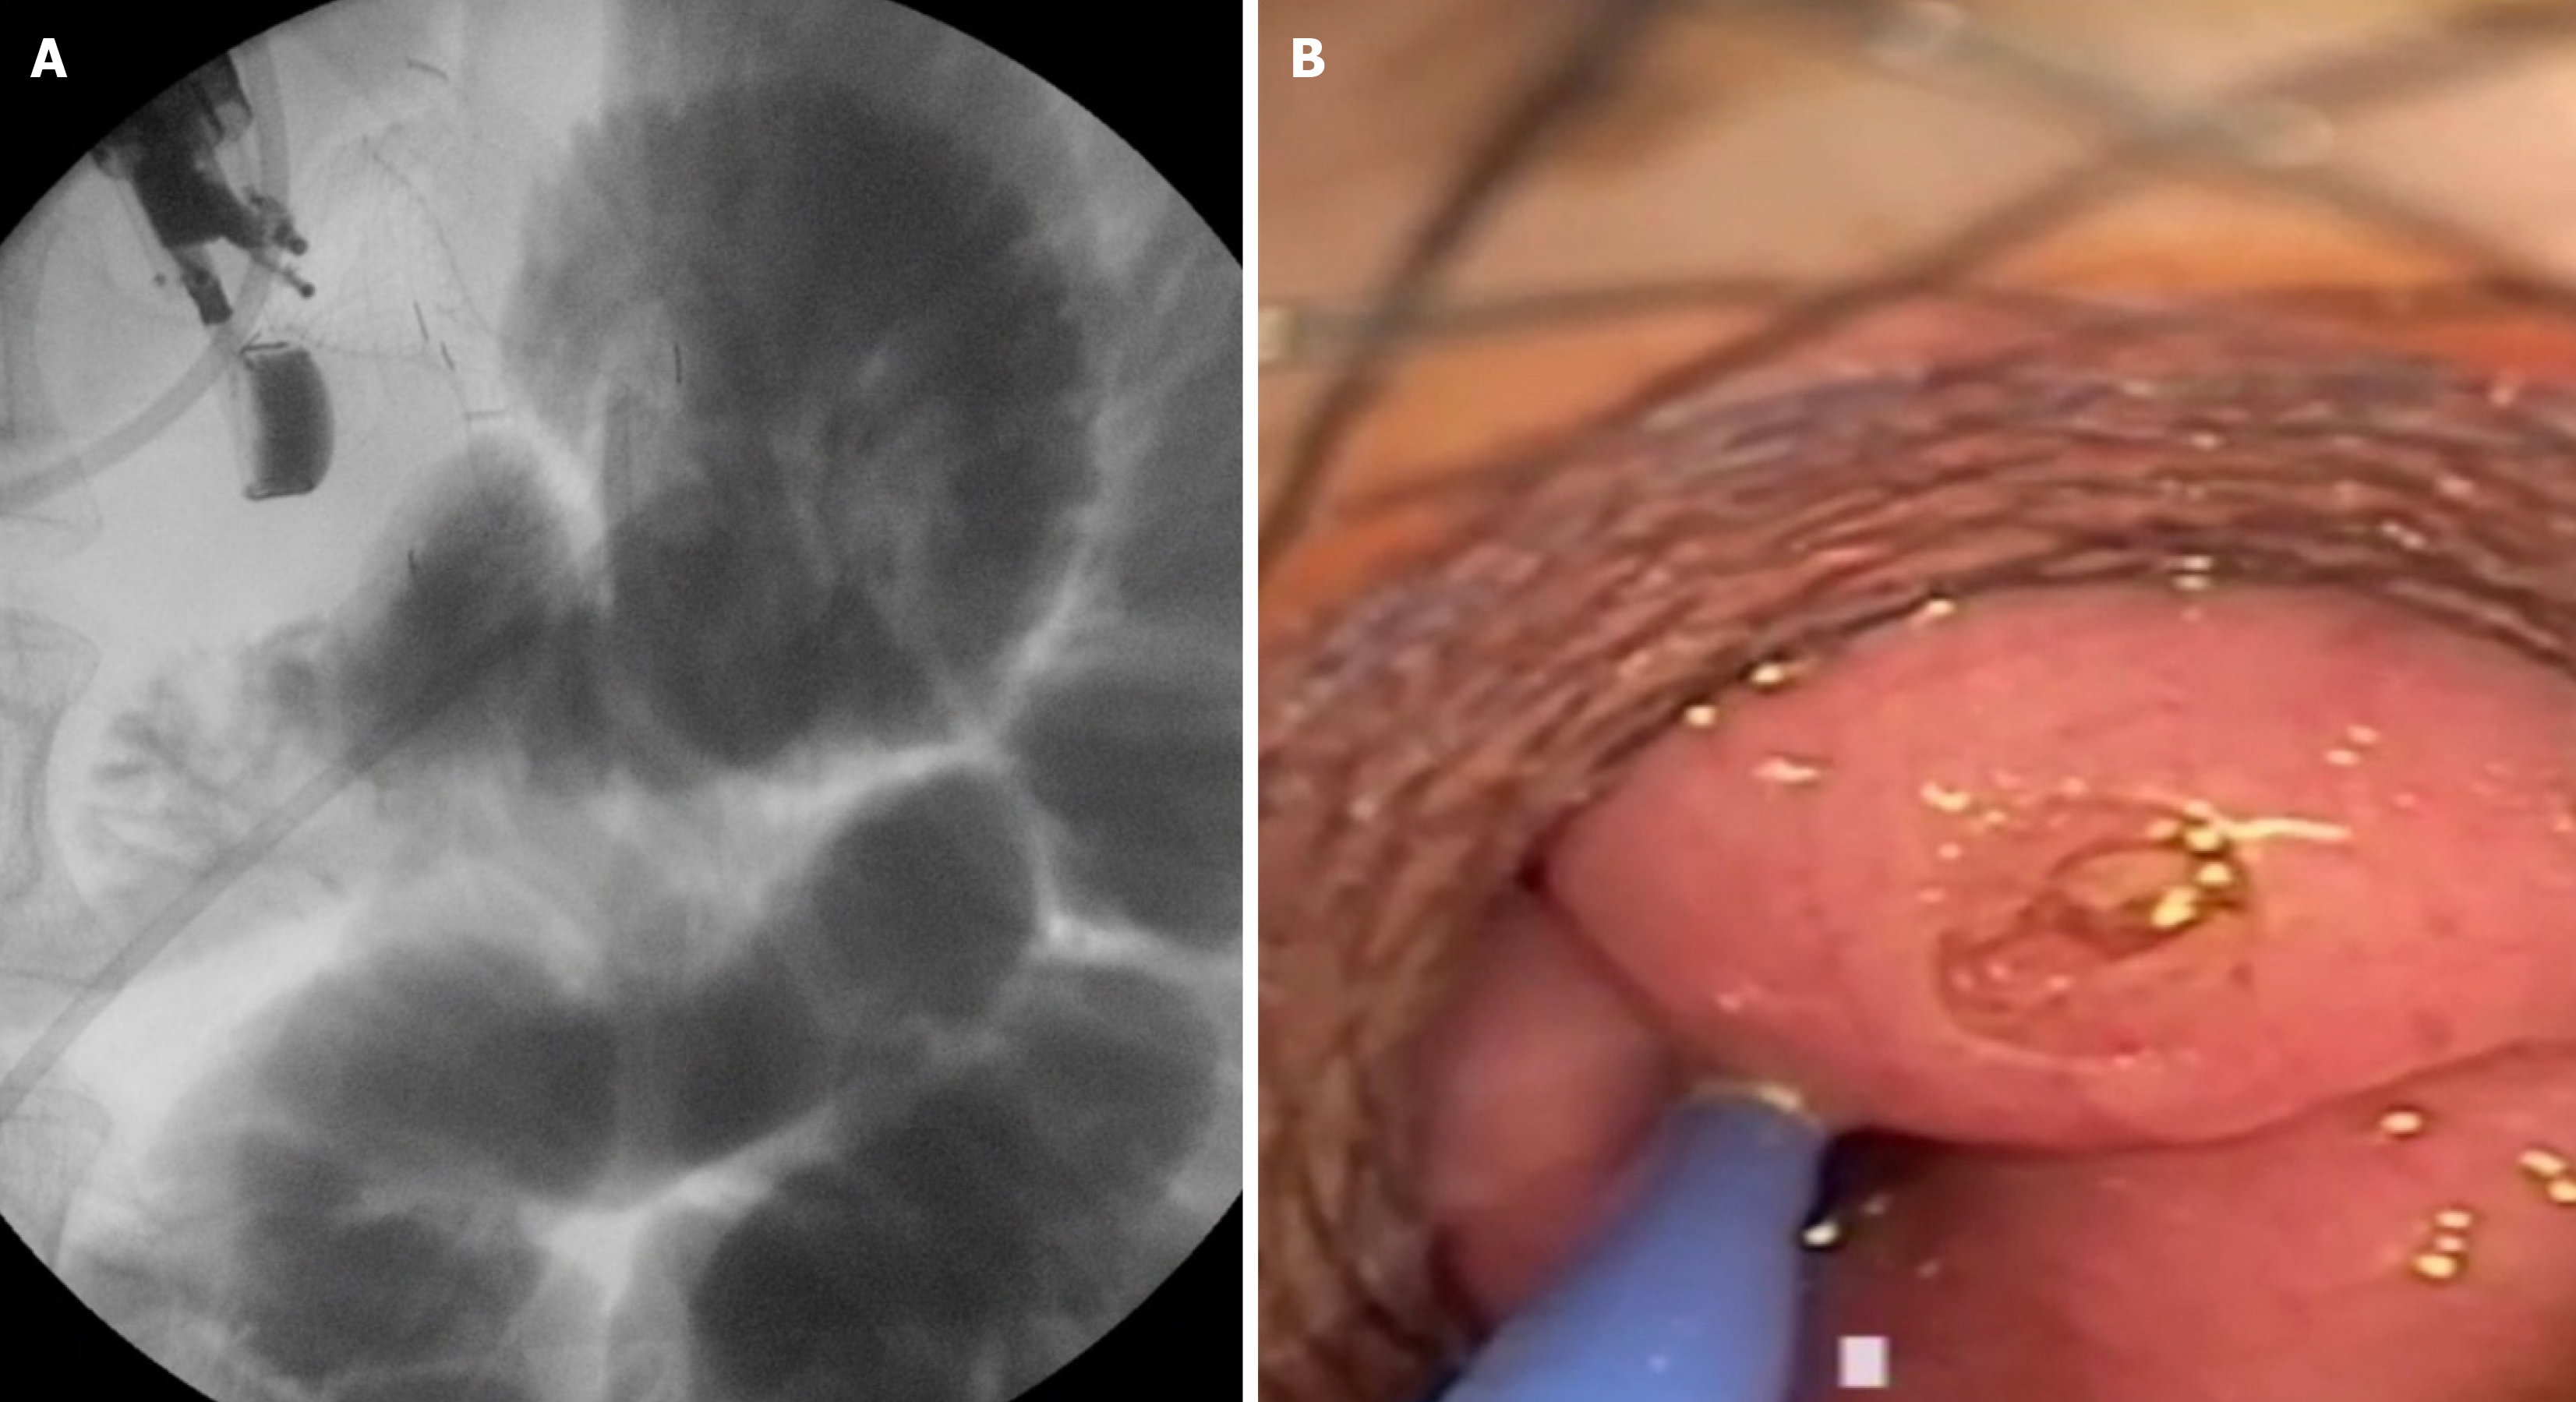

Figure 4 Type II stent misdeployment.

A: Fluoroscopic view demonstrating the distal flange of the lumen-apposing metallic stents deployed in the peritoneum with evidence of an enterotomy; B: Endoscopic view revealing the perforation at the small bowel site, requiring further intervention.